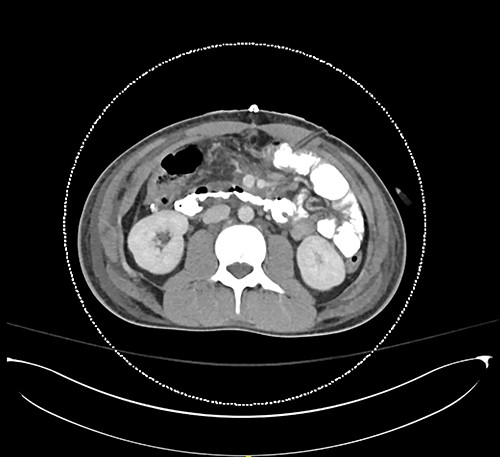

Here, we report a case of a 21-year-old man who was admitted to our hospital following a motor vehicle collision where he was a pedestrian, hit by a car and pushed against the bumper of another car. Upon arrival to the hospital, he was conscious and oriented, with normal vital signs. Abdominal examination revealed ecchymosis over the epigastric area with tenderness, however, no distention was noticed. Focused assessment with sonography for trauma result was positive in the right upper quadrant. His initial blood test results revealed a white blood cell (WBC) count of 26.5 × 109 cells/l and a hemoglobin level of 150 g/l. His serum amylase and lactic acid levels were 92 U/l and 4.53 mmol/l, respectively. His base deficit was 4.3. He underwent abdominal computed tomography (CT) with oral contrast, which showed query duodenal and possible pancreatic transection with active arterial extravasation (Figs 1–3). In addition, CT revealed a comminuted right intertrochanteric femoral fracture without associated vascular injury.

Despite its limitations in distinguishing between duodenal hematoma and duodenal perforation, CT with intravenous and intraluminal contrast remains the gold standard diagnostic test in stable patients with blunt abdominal trauma [1]. In the reported case, CT revealed duodenal and possible pancreatic transection with active arterial extravasation.